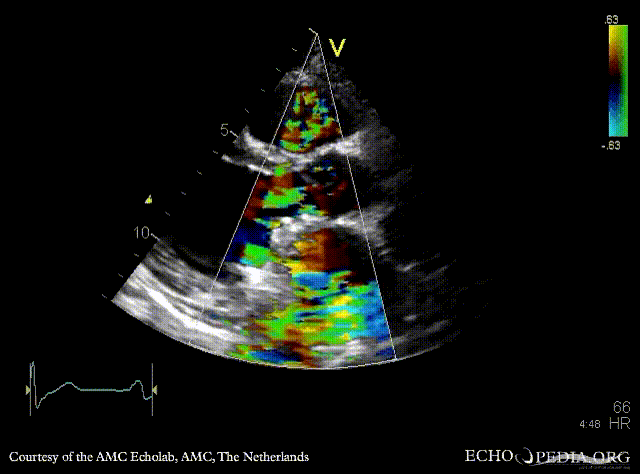

E00596.gif E00597.gif

PLAX: mechanical mitral valve prosthesis, dilated left ventricle and left atrium PLAX with Color Dopler: no mitral regurgitation